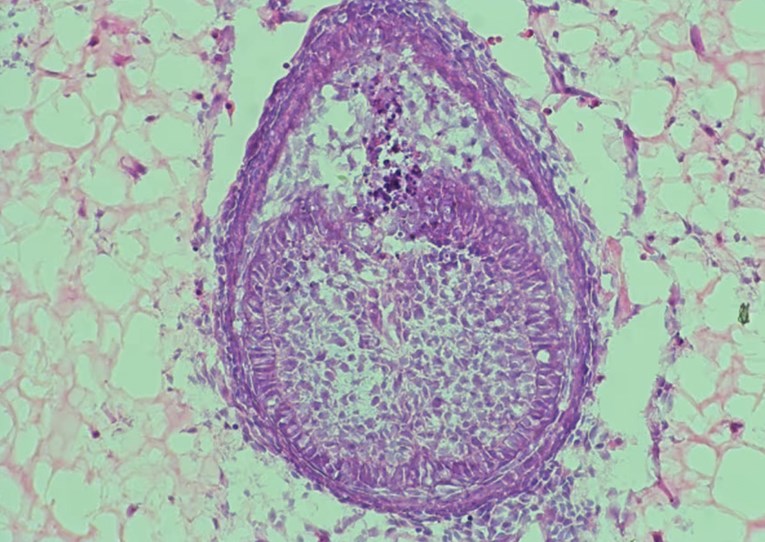

To okruženje, koje znanstvenici nazivaju “skelom”, ključno je za uspjeh. U najnovijoj studiji, umjesto kolagena korištenog 2013., tim sada koristi hidrogel, polimer s visokim udjelom vode. “Prvo prikupljamo stanice iz mišjih embrija, zatim ih miješamo i centrifugiramo kako bismo dobili malu staničnu kuglicu. Zatim ubrizgavamo tu kuglicu u hidrogel i uzgajamo je oko osam dana”, objasnio je Xuechen Zhang, doktorand na King’s Collegeu i koautor studije. Nakon osam dana, unutar hidrogela formiraju se strukture nalik zubima. U prethodnom istraživanju, takvi “zubni zameci” preneseni su u miša gdje su se razvili u zubnu strukturu s korijenom i caklinom.